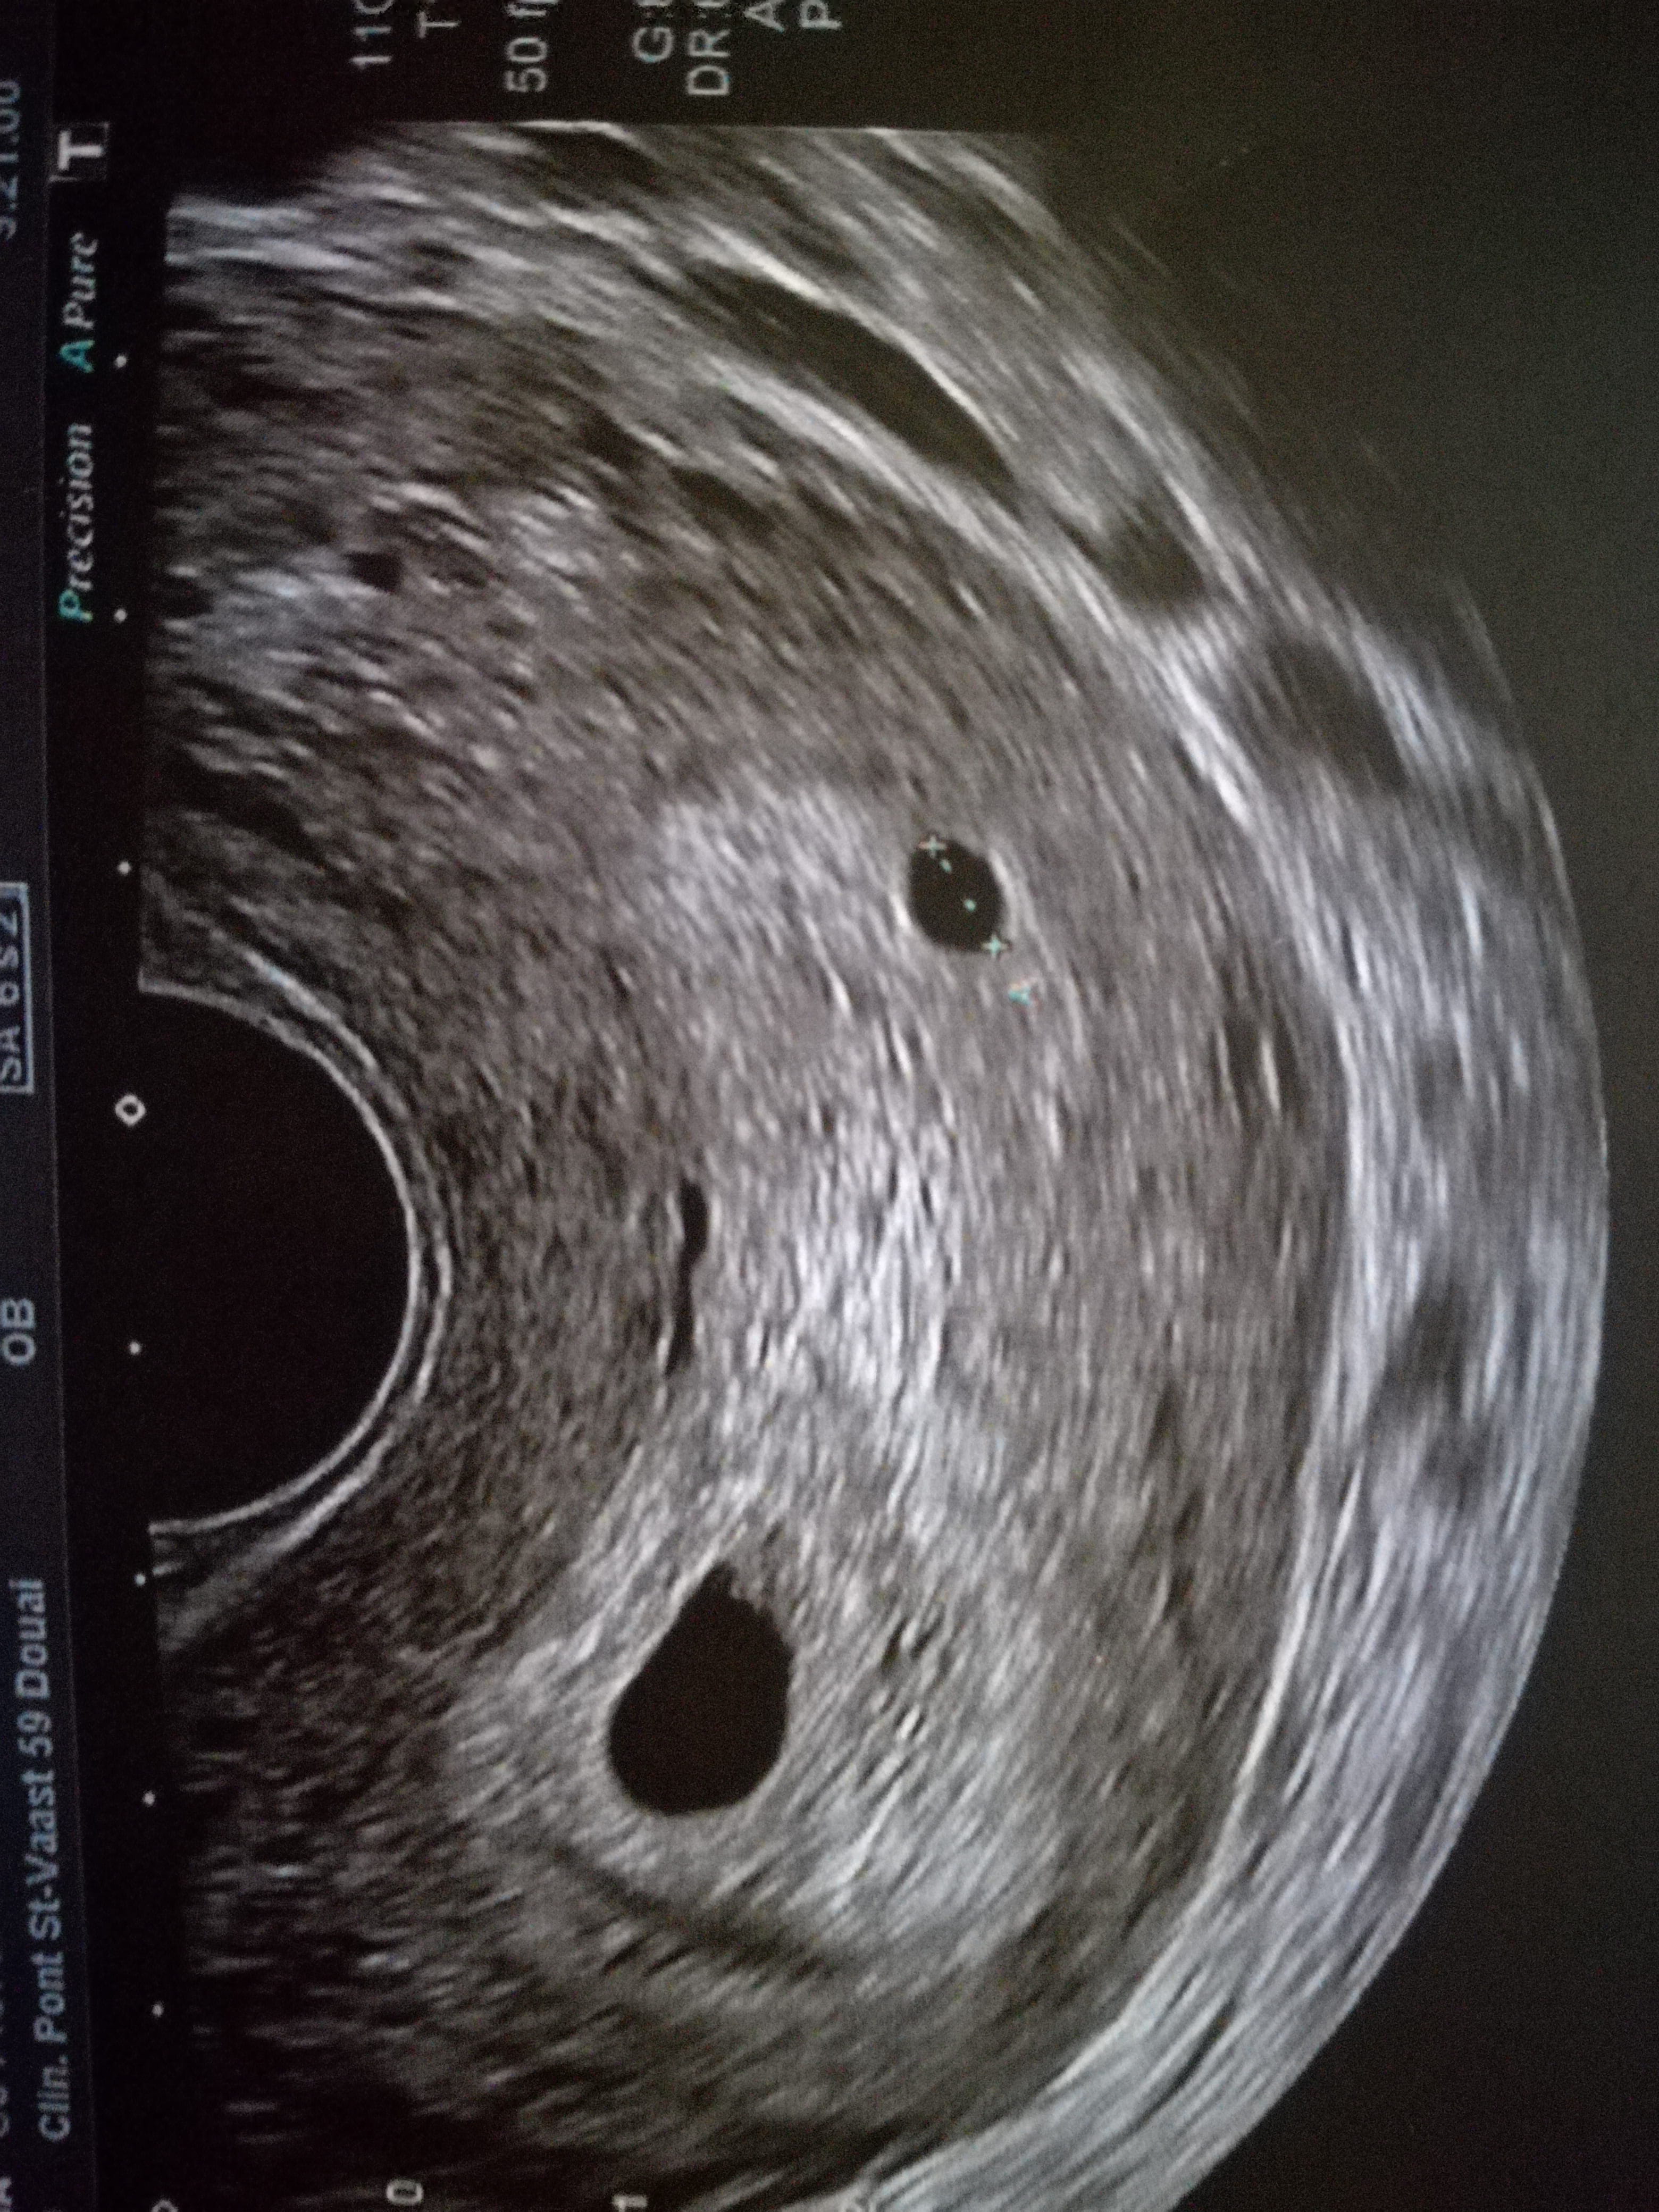

Aujourd'hui je m'adresse en particulier aux mamans de jumeaux voila je voudrai vos avis par rapport a mon eco je suis enceinte de 6 semaines et 2j mon médecin a un gros doute dc rdv pr une nouvelle eco la semaine prochaine pour savoir si c des juju ou pas :) mci a toutes de vos réponses